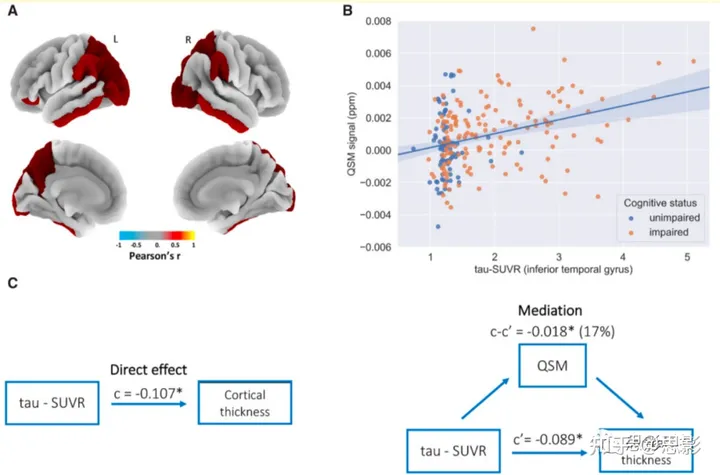

区域分析

在图2A中(并在补充表2中进一步总结;参见补充图5和6A),以3D叠加显示了有符号QSM和tau-PET值之间统计显著相关的区域模式。区域分析确认,全脑分析所识别的正绝对QSM相关性确实由有符号QSM的局部增加驱动,这与铁积累的情况相一致。ITG返回了最强的区域QSM/tau-PET相关性 [左ITG: r = 0.31, P < 0.001 FDR; 右ITG: r = 0.32, P < 0.001 FDR]。

图2 对整个研究队列的区域分析

(A) 显示了有符号QSM和tau-PET信号之间显著的皮尔逊乘积矩相关性(FDR校正P ≤ 0.05)的区域模式。颜色尺度代表皮尔逊相关系数。

(B) 下颞回的平均归一化tau-PET示踪剂摄取作为有符号QSM的函数进行绘制。围绕回归线的半透明区域代表回归估计的95%置信区间。

(C) 中介分析结果的流程图示例(每个模型都将年龄、性别和认知组别作为协变量);c代表tau-PET信号与皮质厚度之间的直接关联强度 [b = –0.107, P ≤ 0.0001, CI: –0.13 to –0.08];c’是考虑到QSM效应后,tau-PET信号与皮质厚度之间的关联强度 [b = –0.089, P ≤ 0.001, CI: –0.12 to –0.06];因此,c-c’就是QSM的中介效应 [b = –0.018, P ≤ 0.001, CI: –0.03 to –0.01,QSM可以解释tau-PET信号对皮质厚度影响的17%(b ratio)]。

在下颞回进行的进一步分析(考虑了半球平均,并考虑了年龄和性别可能的混杂效应,同时将认知状态作为协变量),确认了磁敏性MRI和tau-PET测量之间的正关联(图2B)[tau-PET: β = 0.0009, P < 0.001, 置信区间 (CI) = 0.001 到 0.001; 认知正常和认知受损 (Cog) 组 : β = −0.0002, P > 0.5, CI = −0.001 到 0, 年龄: β = 5.8 × 10−5, P = 0.001, CI = 2.5 × 10−5 到 9.1 × 10−5; 性别: β = 0.0001, P > 0.6, CI = 0 到 0.001]。值得注意的是,下颞回的QSM和年龄之间的关联是显著的。此外,下颞回的tau-PET和QSM值都与皮质厚度测量呈负相关(补充材料)。中介分析表明,即使在模型中包含认知状态,QSM也部分中介了tau-PET和皮质厚度之间的关系[中介效应 = 17%; β = −0.018, P < 0.001, CI: −0.03 到 −0.01](图2C)。包含年龄、性别和教育水平(以年为单位)作为干扰协变量的回归模型显示,下颞回的QSM信号与以迷你精神状态检查(MMSE)量化的全球认知之间存在显著的负相关[QSM: β = −739, P < 0.001, CI: −1067 到 −410; 年龄: β = 0.039, P > 0.3, CI: −0.050 到 0.128; 性别: β = −0.63, P > 0.3, CI: −1.87 到 0.60; 教育: β = 0.12, P > 0.1, CI: −0.03 到 0.27] (补充图7和8)。